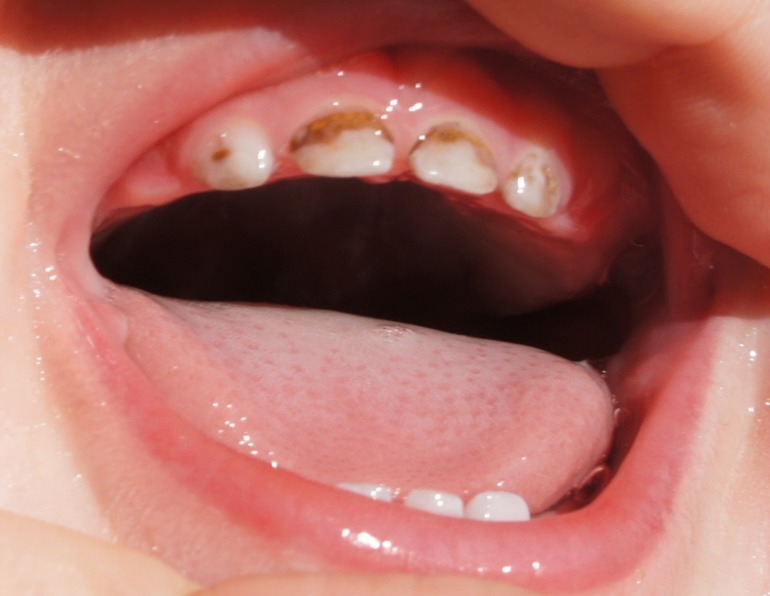

Мы сфотографировали наши посеребренные зубики.

Сразу они не почернели, а через два дня стали такими:

Мы обеспокоены тем, что, возможно, посеребрили нам поздно, и процедура больше навредит, чем принесет пользы. Так ли это, и в целом, каково состояние зубиков на Ваш взгляд?

Здравствуйте.Вы правы- посеребрили Вам уже поздно.Такие зубы необходимо лечить,т.к. серебрение в таком случае не останавливает процесса.